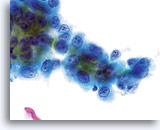

Celkernmembranen zijn verdikt en onregelmatigheden in celkernmembranen zijn golvend, in tegenstelling tot de “rattenbeet”-membranen die ook wel in squameuze laesies gezien wordt.

40x